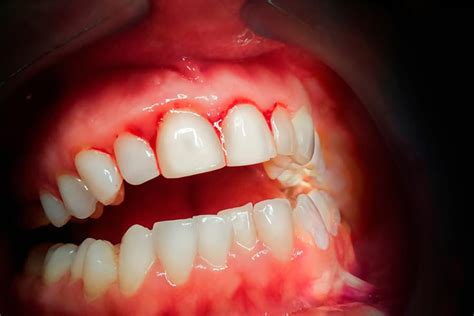

Un estudio reciente llevado a cabo por especialistas de los departamentos de Hematología, Diagnóstico Oral y Radiología Maxilofacial de la Universidad Gazi, ha proporcionado nuevas perspectivas sobre la conexión entre la leucemia aguda (AL) y las manifestaciones de problemas en la cavidad bucal. Destacando especialmente el sangrado gingival de las encías y la presencia de pequeñas manchas o hematomas en la mucosa oral conocidas como petequias y equimosis.

Si tienes costumbre de cepillarte los dientes fuerte o de forma agresiva, seguramente te sangrarán las encías cada vez que te los lavas. Los cambios hormonales, como los que suceden durante la pubertad, la menstruación o el embarazo, también son causas por las que sangran las encías. Los pacientes con diabetes, anemia, hepatitis, cáncer o leucemia pueden experimentar el sangrado de las encías como síntoma de su enfermedad. Incluso existen factores genéticos que también lo promueven. La cardiopatía, el estrés, el bruxismo o la toma de determinados medicamentos también puede provocar este trastorno.

El sangrado de encías inicialmente se atribuye a una limpieza dental insuficiente, pero sabemos que puede ser un síntoma de enfermedades más graves de origen hepático, renal o ser indicativo de diabetes. Podemos decir que la salud bucal es un espejo de la salud general del organismo, en cuanto ofrece pistas reveladoras. Se trata de síntomas y signos que van más allá de sufrir una caries o presentar demasiado sarro entre tus dientes. Una encía sana no sangra, es firme y de color rosa. El sangrado es un síntomas de inflamación de las encías, una alteración qeu se llama gingivitis. Una de las causas puedes encontrarla en una higiene inadecuada que permite a la placa bacteriana adherirse sobre los dientes. El tabaquismo o los cambios hormonales durante el periodo de gestación también producen gingivitis.

Desde Clínica Dental Alberto Romero insistimos mucho en la importancia del cepillado interdental con cepillos interproximales y el uso adecuado del hilo o seda dental. Los aparatos de ortodoncia fija, las prótesis mal colocadas, la menopausia, el estrés, todos pueden provocar gingivitis. El daño hepático, la leucemia, la disfunción eréctil, los partos prematuros, la artritis reumatoide, las patologías renales, los ictus, el infarto de miocardio o la diabetes también se han asociado a esta situación. Esta última, la diabetes, fue una de las primeras enfermedades que se asociaron a la periodontitis. Lo que queremos trasladar a nuestros lectores es que el sangrado de encías es una anomalía que no se debe dejar pasar por alto.

| Afectación Oral | Hipertrofia gingival, sangrado, úlceras |